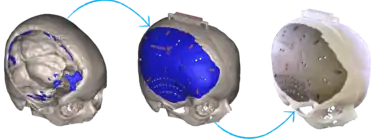

3D-printed implants

3D-printing leverages the power of computer rendering of advanced imaging to tailor implants to each patient, which can then be used to create a physical realization of that implant to use in that individual's surgery.[18][19] 3D-printing of medical devices was first used in the 1990s for dental implants and custom prosthetics but has since been used for various bones and organs such as urinary bladders.[20][21][22]